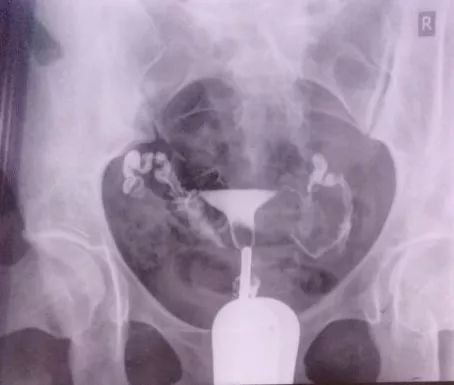

输卵管通畅,伞端粘连

盆腔粘连

这个诊断的准确性很差,可以忽略。只要输卵管是通的,可以试孕。